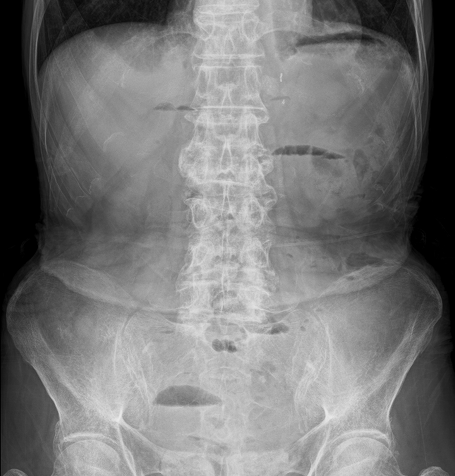

診断・検査方法

• X線撮影